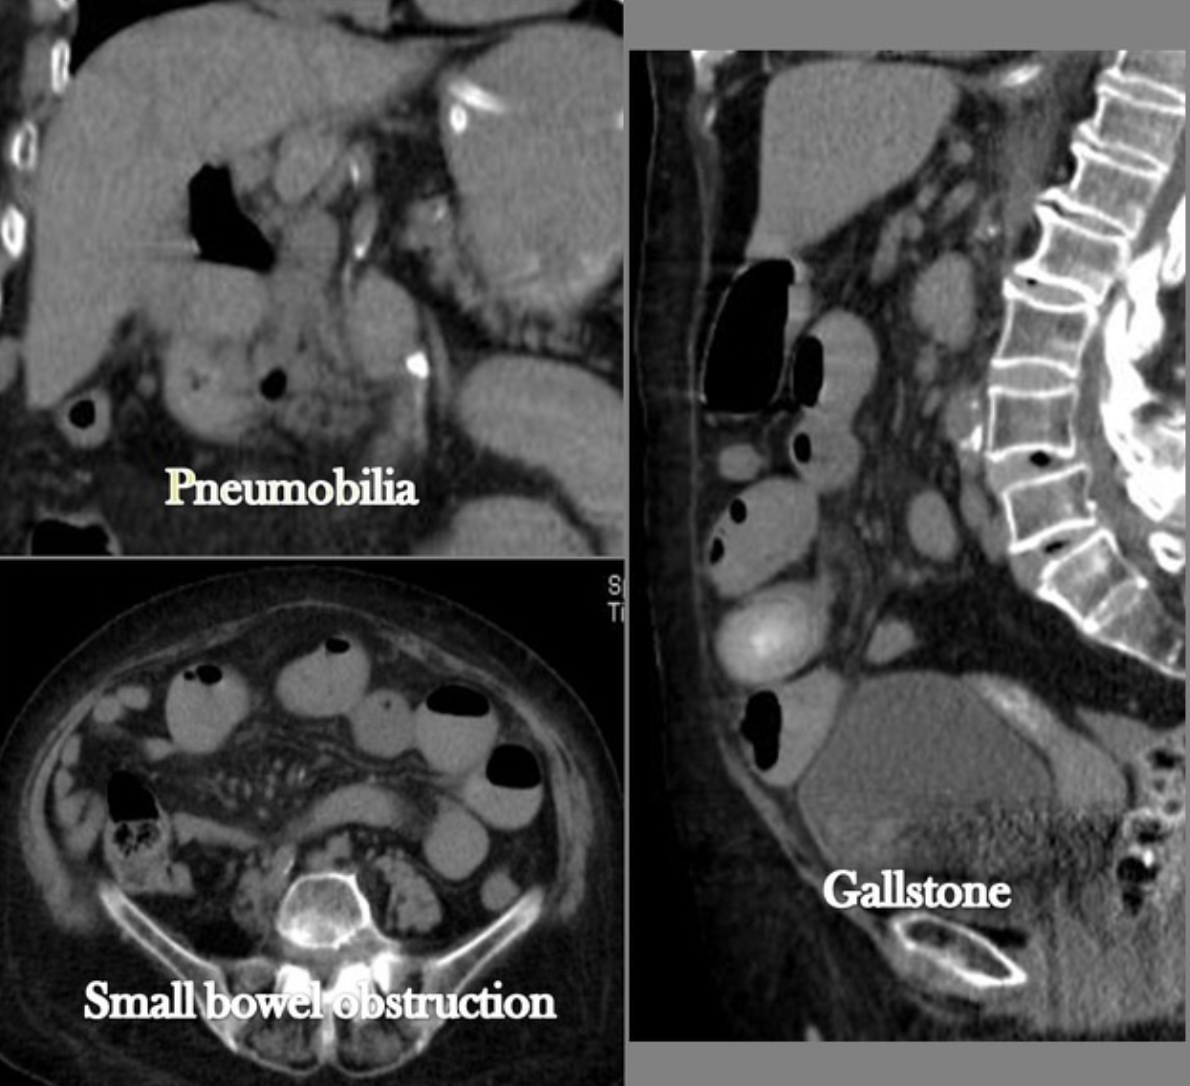

TK jamy brzusznej | triada Riglera: pneumobilianiedrożność jelita cienkiegoektopowy kamień w świetle jelita |

TK jest badaniem z wyboru – najlepiej uwidacznia złóg i jego dokładną lokalizację.